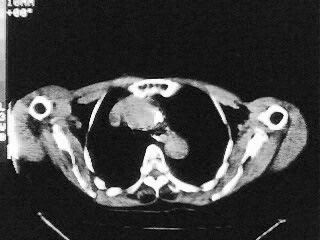

女,79,咳 嗽月余,无其它不适

后纵隔内左心房至肝左叶后方椎体中线偏左巨大软组织包块,其壁均匀比较薄,其内可见宽气液平。

考虑食管裂孔疝。建议钡餐检查